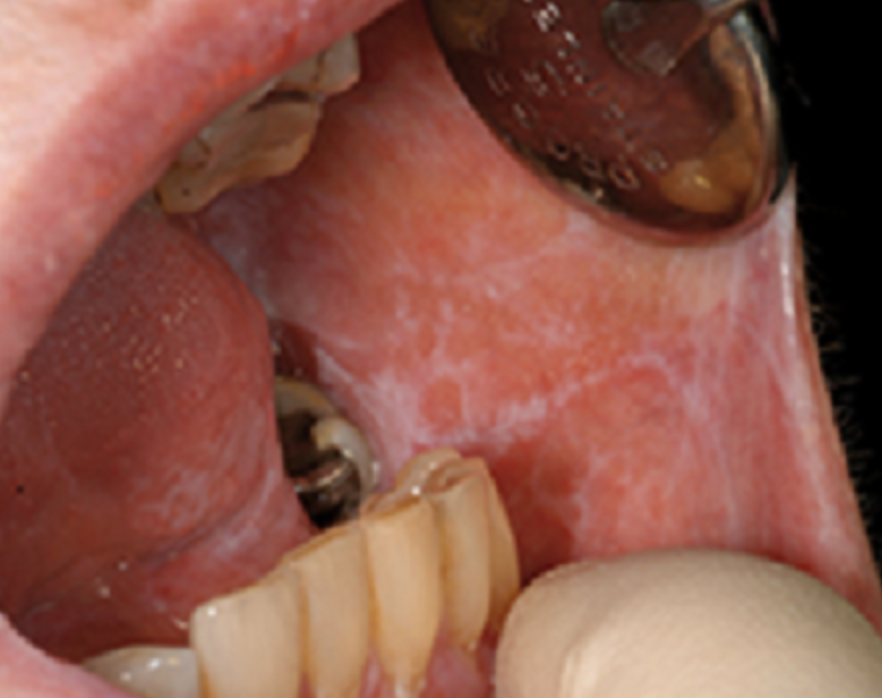

Q

This is?

A

HPV related oral lesion

Because HPV is oncogenic. Referral for biopsy and management.

What are these white striations characteristic of?

Oral lichen planus